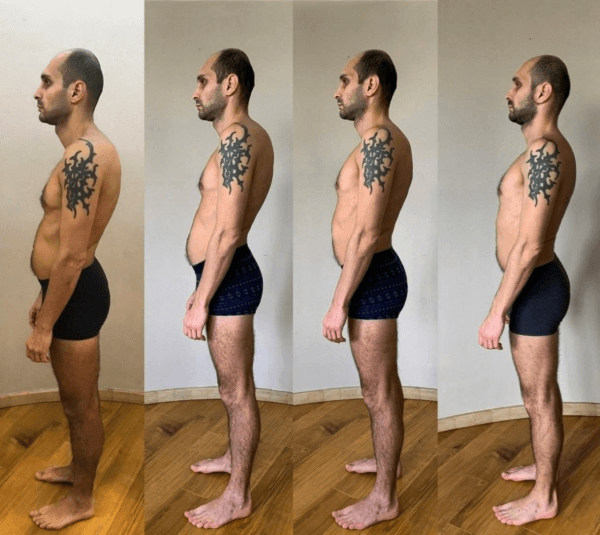

Guardate queste fotografie. Ecco cosa è successo a coloro che non hanno fatto attenzione ai sintomi. Oggi queste persone sono completamente senza speranza, e molti di loro non hanno nessuno su cui contare per le cure. Volete davvero un destino simile?

Silvio Garattini:

— Ognuna di queste persone pensava che non sarebbe mai successo a lei! Ma ecco il risultato: perdita totale di mobilità, paralisi, amputazione — dipendenza a vita dall’aiuto altrui e LA SEDIA A ROTELLE! Più del 90% diventa disabile solo perché non ha preso le giuste misure in tempo. L’USURA DELLE ARTICOLAZIONI INIZIA IN SILENZIO — ignorare il dolore significa buttare la propria vita nel secchio!

Teresa Bellucci, 89 anniUn altro caso chiaro è quello di Alessandro Leone, che a 44 anni ha subito una grave lesione alla colonna vertebrale dopo 15 anni di duro lavoro ed è rimasto costretto sulla sedia a rotelle.

Alessandro, con immensa gioia e speranza, ha deciso di provare il metodo del dottor Silvio Garattini e, già dopo tre settimane, ha sorpreso il suo medico curante. LA COLONNA VERTEBRALE SI È QUASI COMPLETAMENTE RADDRIZZATA, IL DOLORE È SPARITO, E SOPRATTUTTO — HA RICOMINCIATO A CAMMINARE!

Grazie a Hondro Sol, più di 17.000 persone in Italia hanno evitato l’invalidità e recuperato la libertà di movimento. Ecco alcuni pazienti del professor Silvio Garattini:

Silvio Garattini:

— Tutte queste foto dimostrano che “Hondro Sol” restituisce salute alle articolazioni anche in quei casi in cui la diagnosi sembrava una condanna. Senza operazioni, senza dolore insopportabile — tutti i pazienti hanno ottenuto un miglioramento duraturo e sono tornati a una vita piena. QUESTO RIMEDIO HA CAMBIATO COMPLETAMENTE IL CORSO DEL TRATTAMENTO DELLE ARTICOLAZIONI E DELLA COLONNA VERTEBRALE!

Alessandro Marino

Questo rimedio mi ha salvato dalla curvatura e dai dolori alla schiena! Il lavoro sedentario e l'osteocondrosi erano insopportabili, e i medici non sapevano che fare, ma Hondro Sol mi ha letteralmente salvato senza esagerare. La curvatura della colonna vertebrale è una cosa molto seria! Meglio tenere tutto sotto controllo. Ecco il mio risultato:

Sergio Fiorini

Capisco il dolore di chi ha questi problemi. Ho avuto la fortuna di conoscere Hondro Sol sei mesi fa. La mia schiena è completamente guarita in due mesi. Ecco le mie foto: